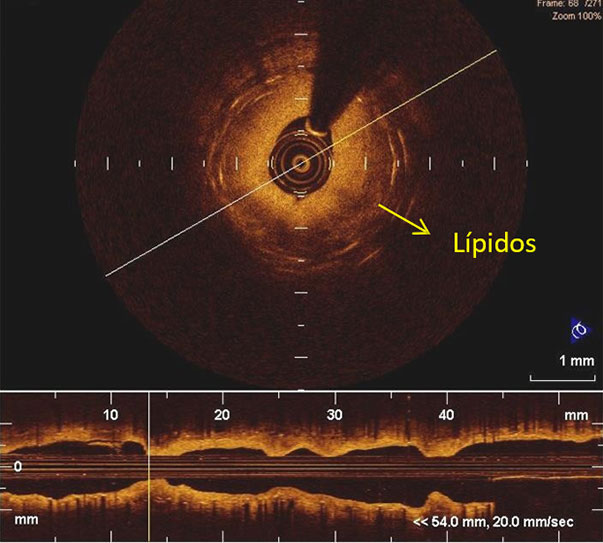

Las imágenes de OCT revelan la presencia de núcleos lipídicos y Neovasos, signos típicos de Neoaterosclerosis